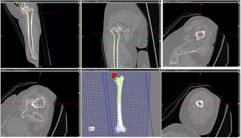

52歳 女性 両側変形性股関節症

![]() |

| 手術時間 | 83分 |

| インプラント |

|

| 設置精度 |